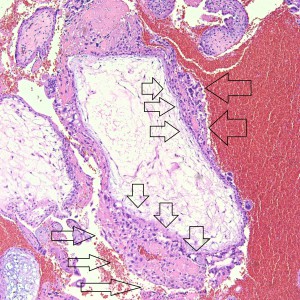

This large hydropic villus with central cistern also demonstrates an important finding: the loss of polarity of the surrounding trophoblasts with circumferential proliferation of variably atypical trophoblastic cells (arrows).